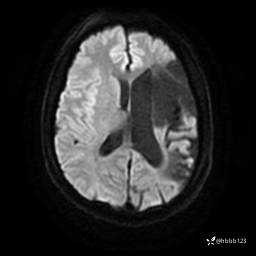

患者男,43岁。

简要病史:癫痫患者复诊,昨日发作5-6次,建议住院进一步治疗。

入院完善脑癫痫组合序列:

T2 Flair: